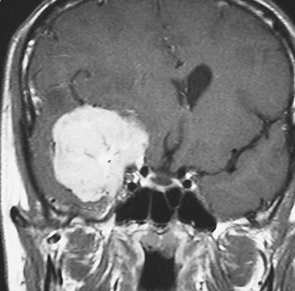

典型的な髄膜腫

この髄膜腫は中程度の大きさのものです。円蓋部髄膜種という最も多い最も手術の簡単なタイプです。麻痺や失語症やてんかんなどの症状はありません。とても美しくて若い女性の髄膜腫でしたが,子供に遺伝はしませんし,癌などと違ってタバコなどこれといった原因がなくて発生するものです。

MRIでの髄膜腫の見え方は撮影の仕方によっていろいろです。左からT1強調画像,T2強調画像,フレア画像といいます。腫瘍の横に小さく白い領域がありますが,これは脳の腫れた部分で脳浮腫といいます。髄膜腫があると周囲に脳浮腫が生じることがあります。

最も見やすいのが,ガドリニウム造影剤を注射して撮影するものです。一般的に髄膜腫は造影剤で白く映し出されます。この腫瘍は左脳側にあります。MRIの軸面という輪切りの写真では左右が逆になりますから注意してください。脳を下から見た図になっています。MRIはいろいろな方向から腫瘍を見ることができますが,右は冠状断という正面から見た図です。よく見ると腫瘍の上と下のはじっこに線状に糸を引いたように造影される部分があります。これをテールサイン(しっぽのサイン)といいます。腫瘍が硬膜に沿って延びている可能性があることを示しています。